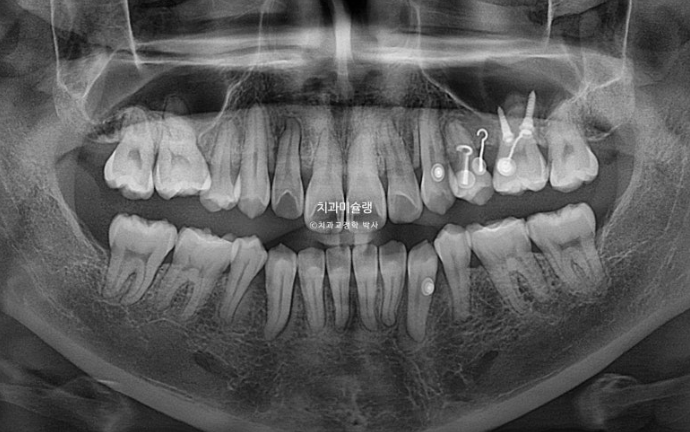

엑스레이에서 보이듯 이미 쓰러진 일부 어금니들을 세우고

미세하게 남은 발치공간을 닫고 교합을 안정화 시키고자 재제작에 들어갑니다.

어금니 쓰러진 부분들은 추가장치로 다시 세워 치근평행도는 좋습니다.

발치공간이 치실 헐겁게 들어갈 정도가 아직 남았고 구치부 교합도 좀 더 개선하고자 2번째 재제작에 들어갑니다.

2년 3개월의 치료기간동안 치근흡수는 없고 치근평행도는 양호합니다.